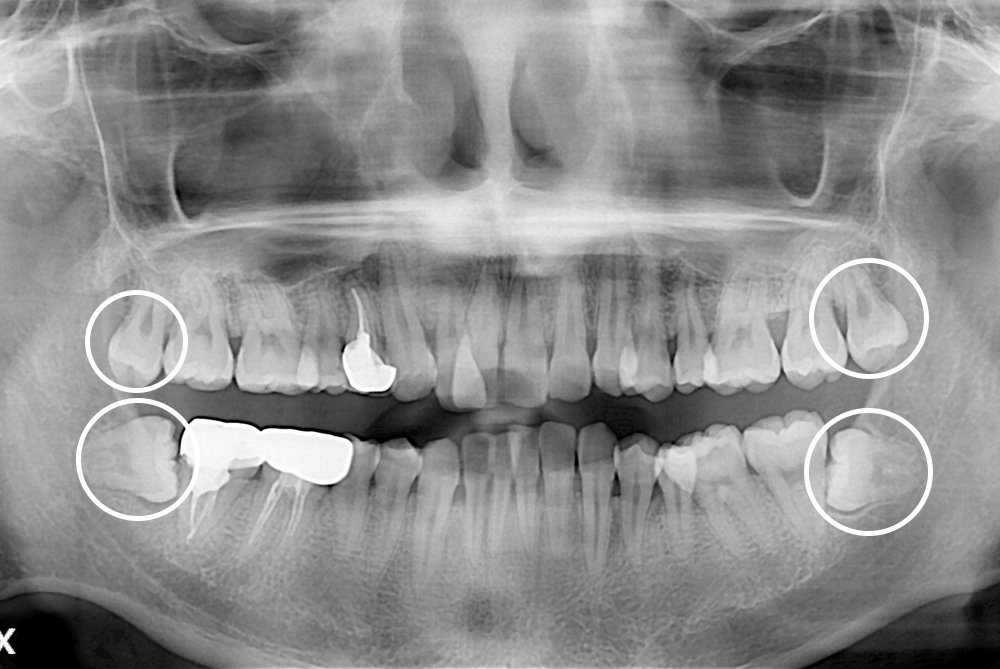

[사랑니] 매복 사랑니 발치

치료전 : 2019-03-11

세종치과는 구강악안면외과학 박사이신 원장님이 발치하는 치과입니다.